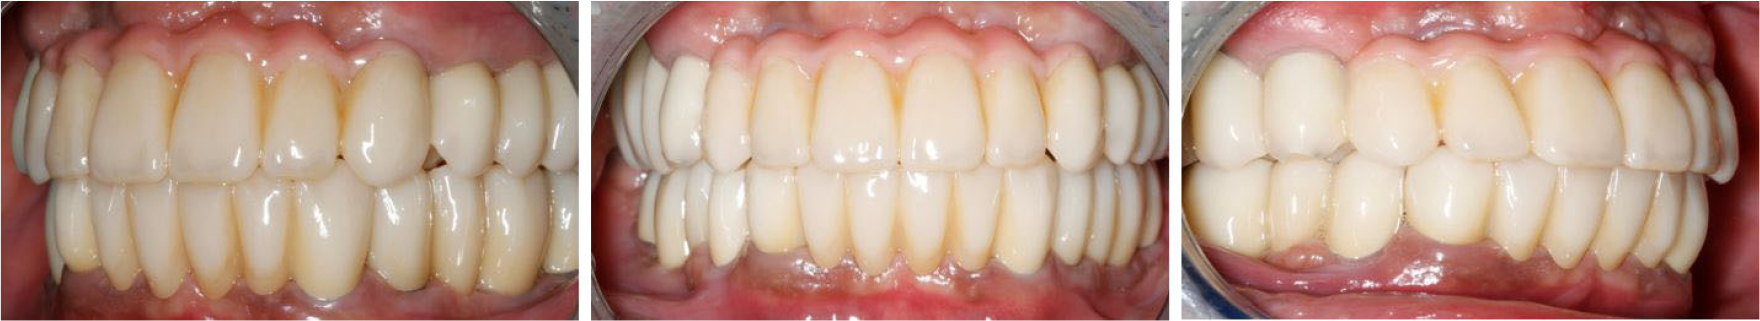

The treatment was completed without any discomfort after delivery of the final prosthesis because the vertical dimension or occlusal surface shape of the prosthesis was exactly the same as that of the provisional prosthesis (Figs. 10 and 11).